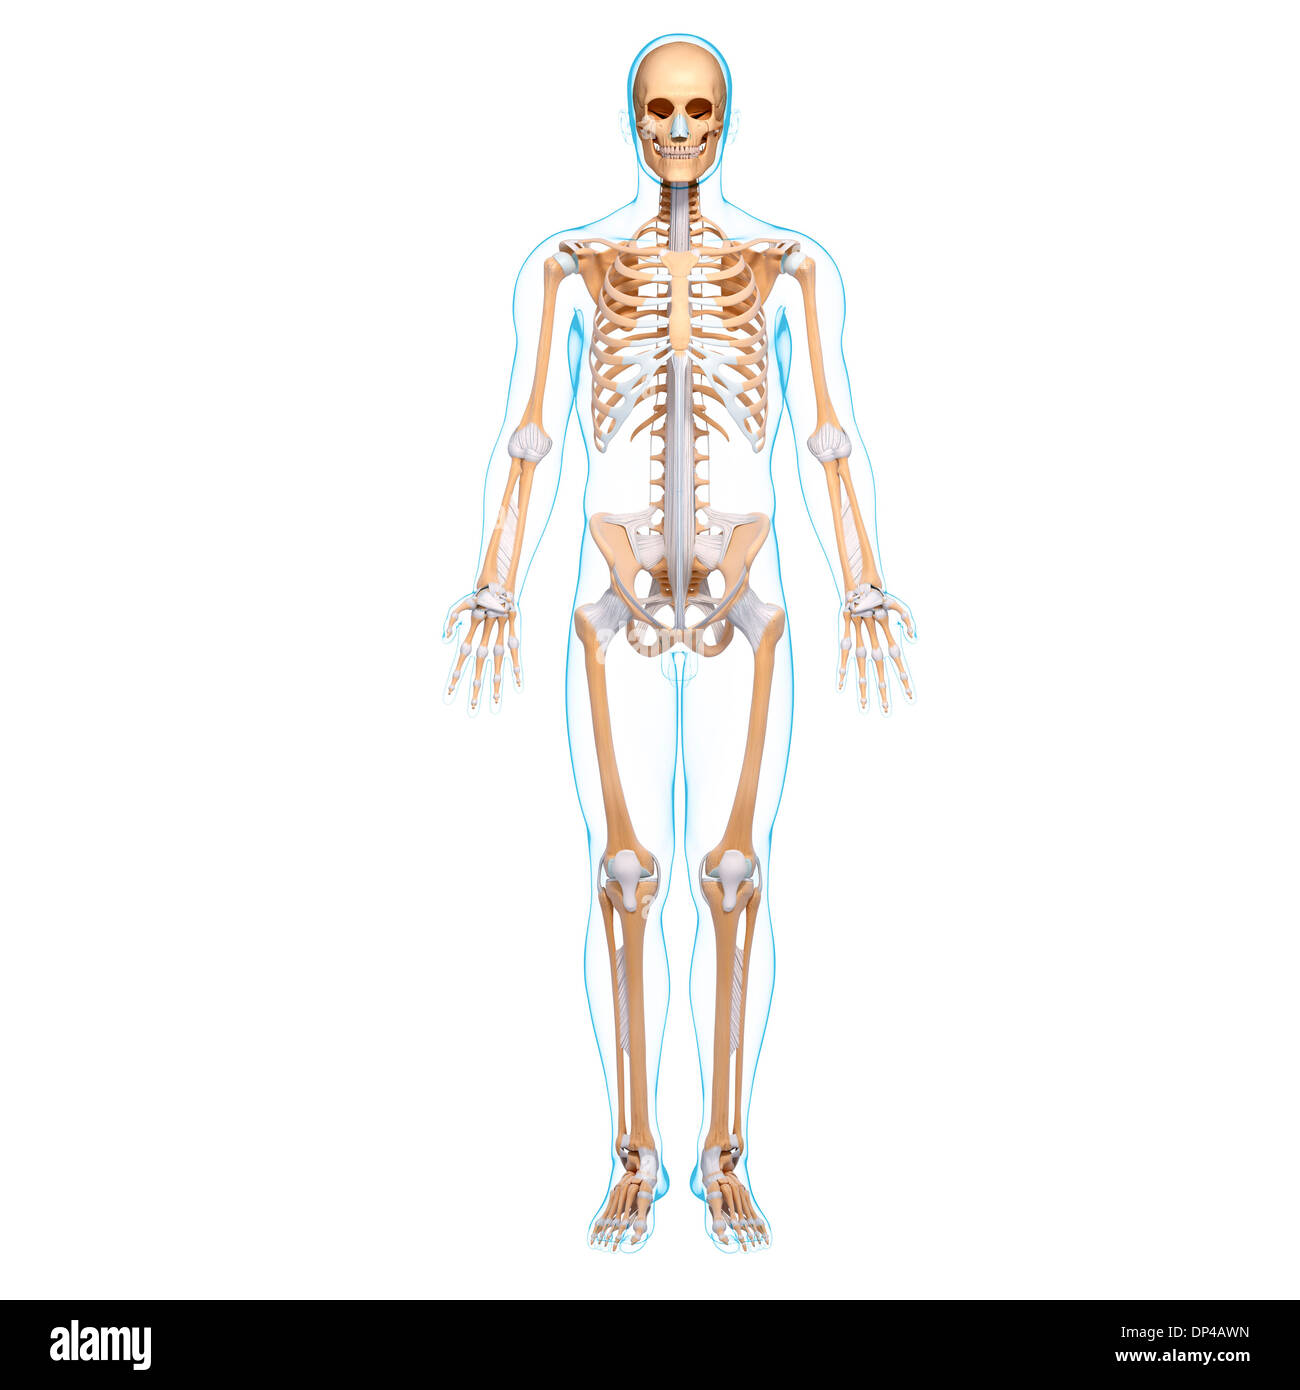

, Artwork Banque D'Imageshttps://www.alamyimages.fr/image-license-details/?v=1https://www.alamyimages.fr/artwork-image65249905.html

, Artwork Banque D'Imageshttps://www.alamyimages.fr/image-license-details/?v=1https://www.alamyimages.fr/artwork-image65249905.htmlRFDP4AWN–, Artwork